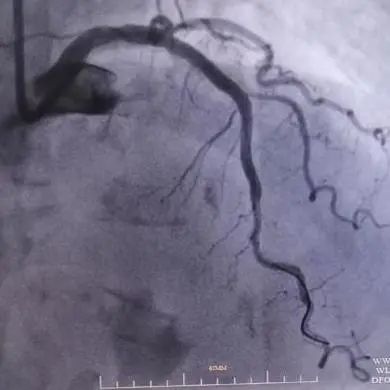

入院后冠脉造影提示:左主干体部狭窄约20%,前降支近段至中段血管迂曲,局部可见明显成角伴钙化,最重处狭窄80%。回旋支细小,管腔未见明显狭窄。右冠全程弥漫性粥样硬化伴钙化,近段狭窄约40-50%,远段狭窄约60%,左室后支开口狭窄50%。

手术由黄进宇童国新两位教授联合实施。首先在前降支病变处置入3.5×12mm冲击波球囊,以4atm压力膨胀紧贴血管壁,然后启动脉冲发生器,持续激发10个脉冲完成第1周期,可见球囊逐渐膨胀充分,随后以6atm扩张冲击波球囊,可见球囊扩张满意。重新定位冲击波球囊,重复启动脉冲,总共7个周期脉冲优化冲击波碎石效果。

复查IVUS清晰可见病变处环形钙化多处断裂,局部未见明显夹层,获得较大管腔,已满足支架植入条件。遂于左前降支近段成功植入3.0×18mm、3.5×15mm药物洗脱支架2枚。复查造影及IVUS提示支架膨胀良好,未见夹层及边支丢失,手术取得圆满成功。

图2.病变处理前/普通球囊预处理中/冲击波球囊预处理中的冠脉造影图片对比